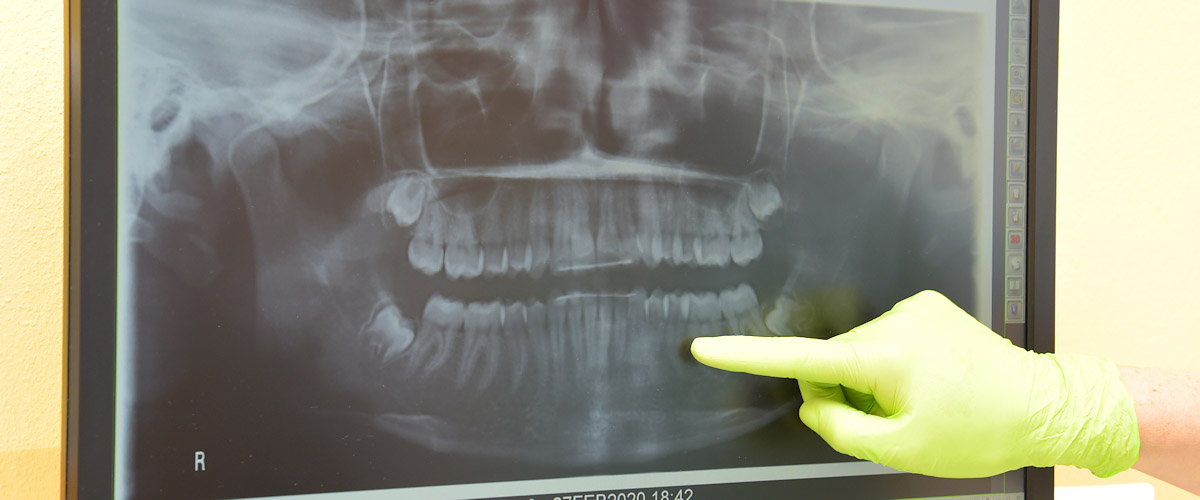

Wenn der Zahnnerv (Pulpa) sich entzündet, kann es zu Schmerzempfindlichkeit bei heiß und kalt oder zu Dauerschmerzen kommen. Der Zahnnerv kann aber auch unbemerkt absterben, was häufig erst bei einer Röntgenuntersuchung festgestellt wird.

- Besonders wichtig für eine optimale Reinigung ist die exakte Bestimmung der Wurzelkanallänge. Zusätzlich zur traditionellen Röntgenaufnahme bieten moderne computergestützte elektrische Verfahren einen hohen Grad an Präzision.